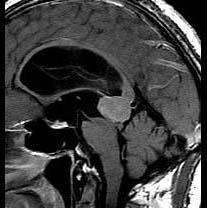

问题 15岁,男,头痛、呕吐,步态不稳,眼球震颤,性发育异常,MRI检查如图,最可能的诊断()

选项 A.松果体钙化 B.松果体瘤 C.脑膜瘤 D.生殖细胞瘤 E.畸胎瘤

答案 B